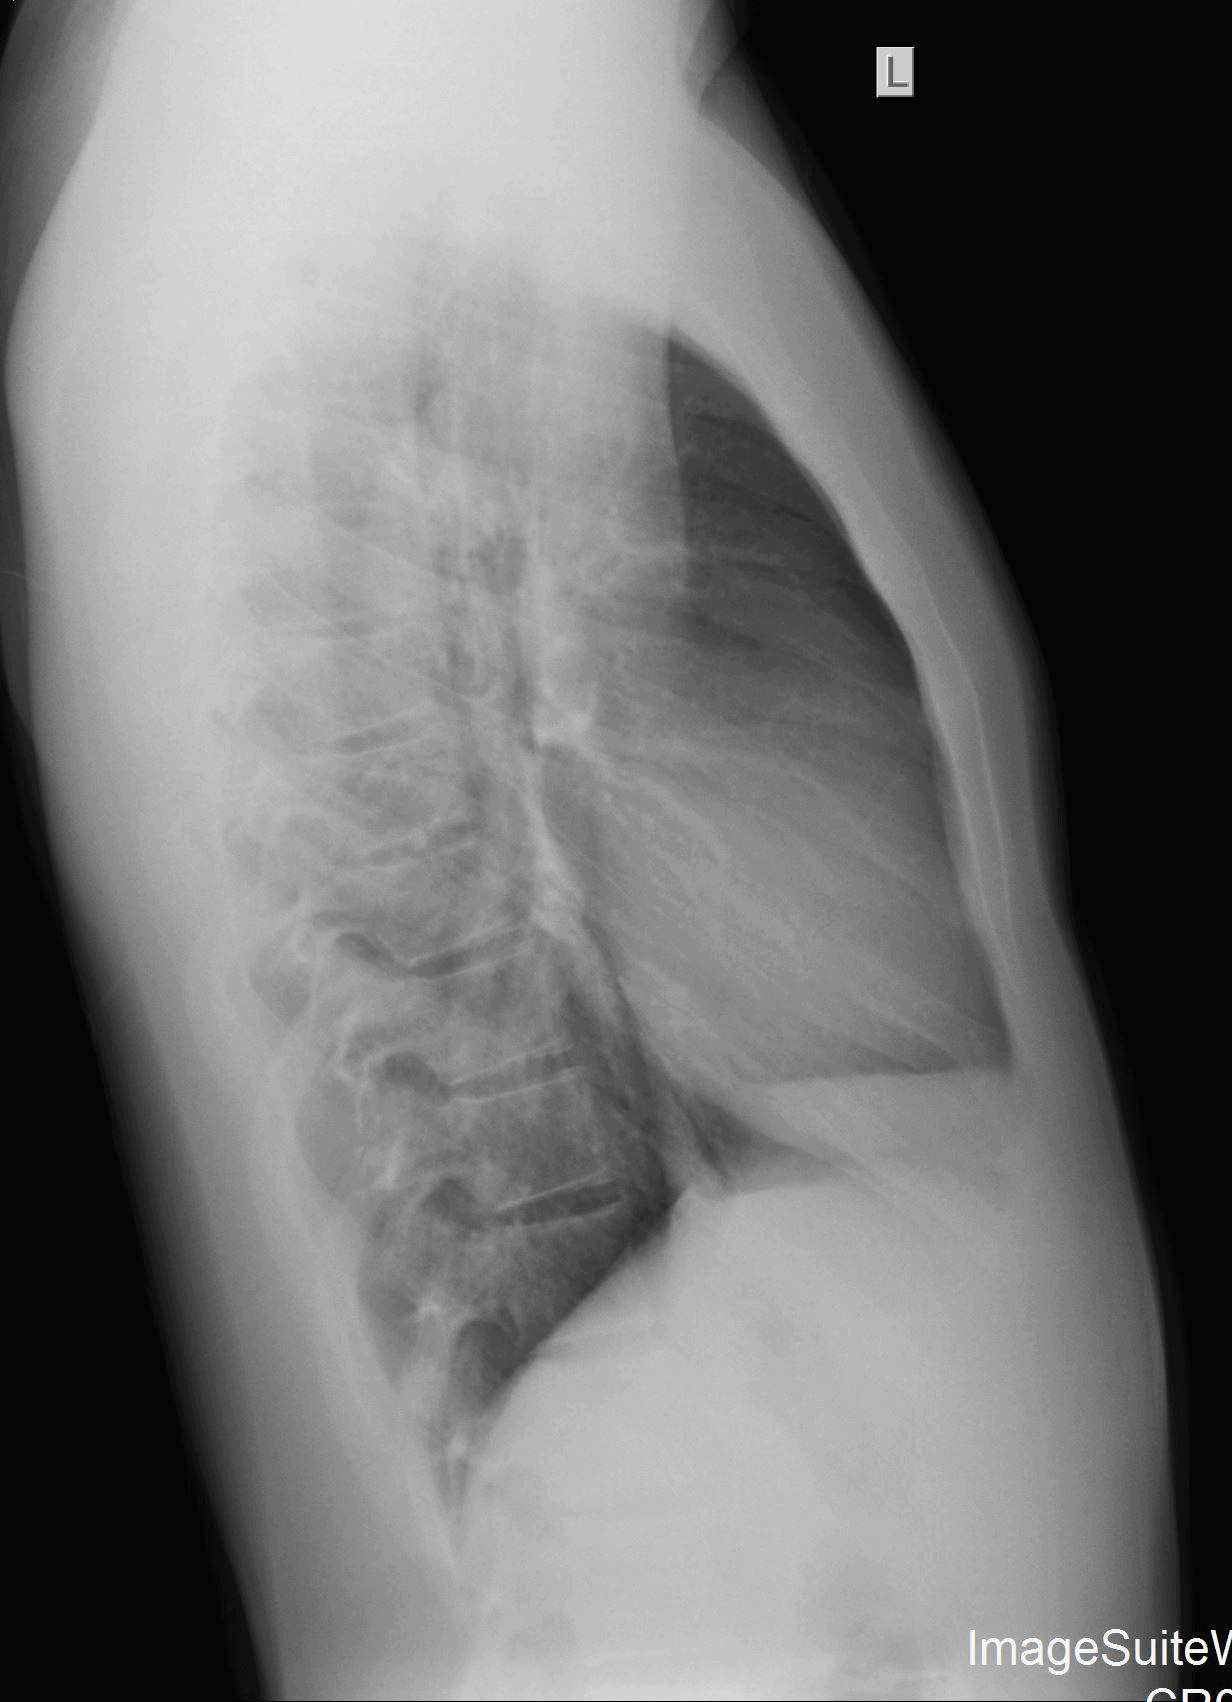

The patient is a 9-year-old girl who is brought in by her parents shortly after choking on a chicken nugget. They are concerned because even though she stopped gagging, she complains that it feels “like there’s something stuck in there.”

View the images, ordered to rule out a lodged foreign body, and consider what the diagnosis and next steps would be. Resolution of the case is described on the next page.